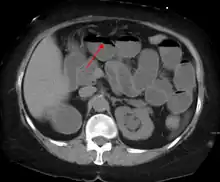

A small bowel obstruction as seen on CT

The main diagnostic tools are blood tests, X-rays of the abdomen, CT scanning, and ultrasound. If a mass is identified, biopsy may determine the nature of the mass.

Radiological signs of bowel obstruction include bowel distension and the presence of multiple (more than six) gas-fluid levels on supine and erect abdominal radiographs. Ultrasounds may be as useful as CT scanning to make the diagnosis.[17]

Contrast enema or small bowel series or CT scan can be used to define the level of obstruction, whether the obstruction is partial or complete, and to help define the cause of the obstruction. The appearance of water-soluble contrast in the cecum on an abdominal radiograph within 24 hours of it being given by mouth predicts resolution of an adhesive small bowel obstruction with sensitivity of 97% and specificity of 96%.[18]